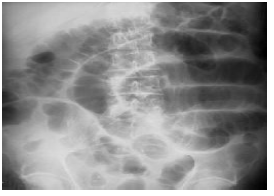

Q.82. A patient presented with severe constipation during his post- surgery follow-up. His X-ray abdomen is attached below. What is the most appropriate management for this patient?

Correct Answer : C